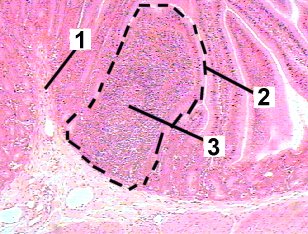

This figure is a high magnification of a Peyer's patch in the ileum.

Fig 41-005